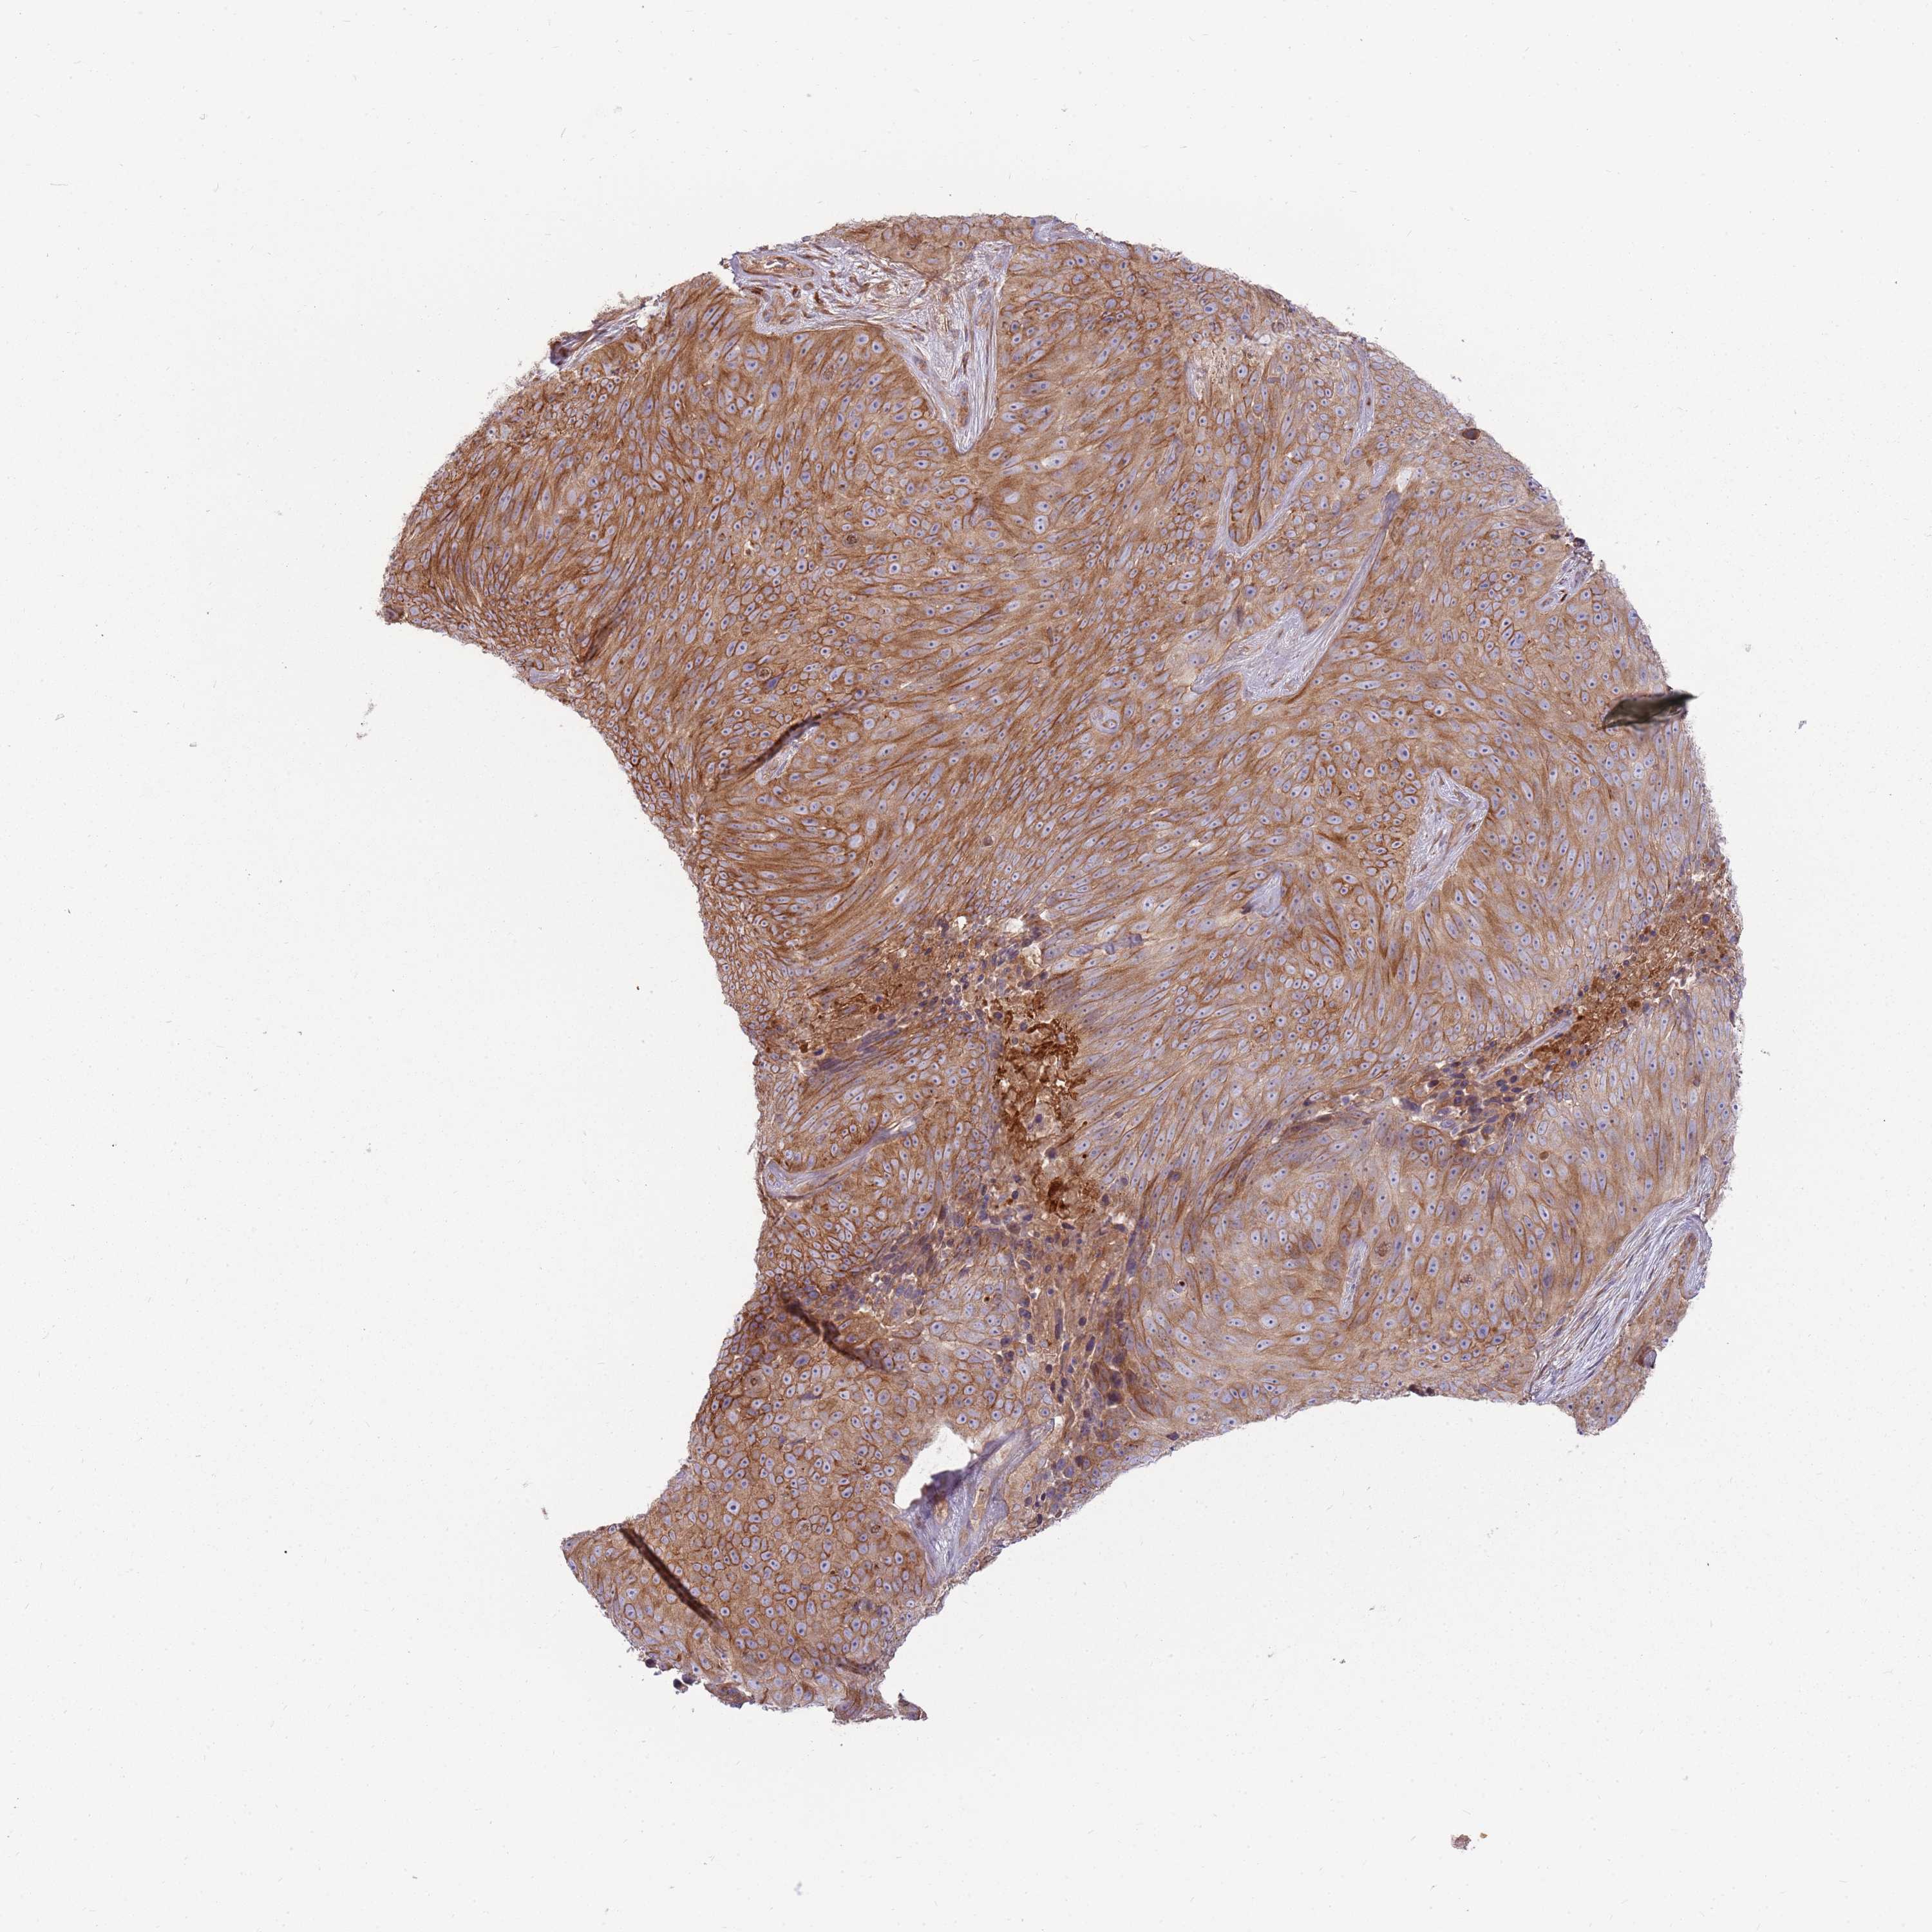

Basal cell and squamous cell cancer

SKIN CANCER - Protein expressioni

A mouse-over function shows sample information and annotation data. Click on an image to view it in a full screen mode. Samples can be filtered based on level of antibody staining by selecting one or several of the following categories: high, medium, low and not detected. The assay and annotation is described here.

Each image is clickable and will lead to virtual microscopy that enables deeper exploration of all samples and also displays staining intensity scores, fraction scores and subcellular localization as well as patient and tissue information for each sample.

Antibody HPA048904

Staining

High

Intensity

Strong

Quantity

>75%

Location

Cytoplasmic/membranous

Basal cell carcinoma